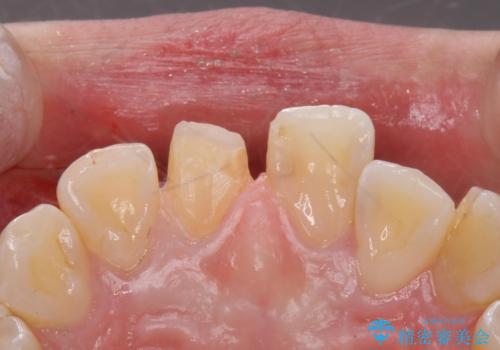

- 前歯のかぶせ物の色が気になるとのことで来院された患者様です。

セラミッククラウンで作り変えていきます。

- 右上1: 仮歯/11,000円、ジルコニアクラウン(スタンダード)/121,000円 合計132,000円(税込)費用は治療当時の料金となります

色・形ともに改善され、大変喜んでいただけました。